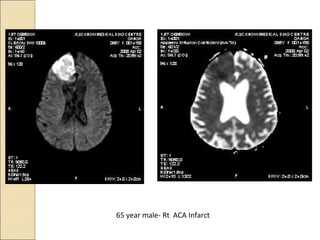

65 year male- Rt ACA Infarct

Evaluation of acute stroke on DWIEvaluation of acute stroke on DWI

The DWI and ADC maps show changes

in ischemic brain within minutes to few

hours

The signal intensity of acute stroke on

DW images increase during the first

week after symptom onset and decrease

thereafter, but signal remains hyper

intense for a long period (up to 72 days in

the study by Lausberg et al)

The ADC values decline rapidly after the

onset of ischemia and subsequently

increase from dark to bright 7-10 days

later .

This property may be used to

differentiate the lesion older than 10 days

from more acute ones .

 Chronic infarcts are characterized by

elevated diffusion and appear hypo, iso or

hyper intense on DW images and

hyperintense on ADC maps